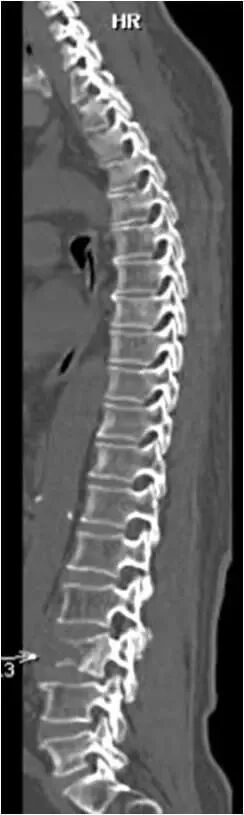

高清全方位骨科检查

西门子双源CT(SOMATOM Drive)可以用于全方位骨科检查。最新ADMIRE基于原始数据域的迭代重建技术,不仅可以大幅降低图像噪声,还可以降低辐射剂量。